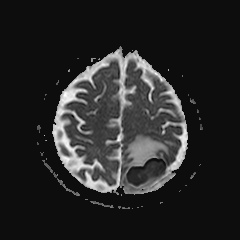

Caso neurorradiología

Paciente de 60 años con cuadro de 1 semana de evolución consistente en tropiezos frecuentes y alteración en la movilidad del miembro

inferior derecho. No refiere

cefalea u otros síntomas asociados, no pérdida de peso, no náuseas o emesis, no

sudoración nocturna. Antecedentes de hipertensión arterial y diabetes.

Resonancia magnética